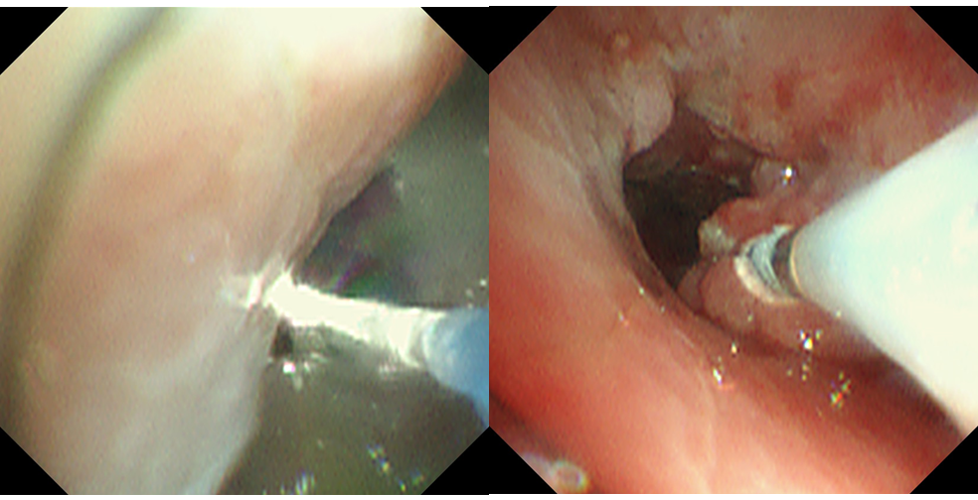

使用激光消融及冷冻消融

此次治疗的患者虽然在电子支气管镜检查及胸部CT均已明确异物诊断,但由于呛咳时间不明,加上异物较大,而且异物周围已存在大量肉芽组织包裹,同时伴随大量肉芽组织及疤痕增生,导致气管重度狭窄,这种情况下如果触碰极易出血,给异物的取出增加了难度。而激光消融可在狭窄的支气管内对异物进行拆分,将异物分解成多个碎片取出,因此减少了出血的风险。

Nd:YAG激光消融术因高效、快捷、微创、无出血风险、术后并发症少等优势,近年成为推崇的热消融新方法。对比创伤较大的外科手术,其对手术麻醉深度要求更低。冷冻不仅可有效去除增生的肉芽组织,还可以减轻术中出血。支气管镜下热消融加冷冻消融治疗成为当前相对新颖、安全、简便、有效的治疗方式。本次手术患者经上述治疗后,气道异物完全取出,肉芽组织减少,管腔通畅,术后达到了预期治疗效果。目前我科已经多次开展类似手术操作,先后在支气管内取出豌豆、动物骨架等较大、质地较硬、取出较困难的异物,为河源当地的患者减轻痛苦,同时降低了治疗费用。